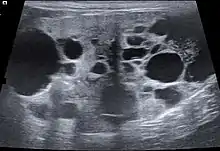

Echographie

L'échographie permet de visualiser plus finement l'architecture du parenchyme rénal. Outre les modifications de taille et de forme, on peut détecter des kystes rénaux, des malformations, des lésions inflammatoires ou tumorales, des urolithiases, etc. Néanmoins, si l'échographie peut permettre d'identifier des lésions rénales, elle ne permet pas forcément d'en identifier la cause[27]. Au moyen de l'échographie doppler pulsée, on peut aussi mettre en évidence des anomalies vasculaires[28],[29].